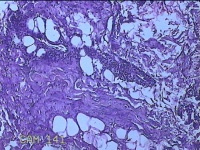

左侧腋下结节

性别

女

年龄

22岁

临床诊断

皮下结节;皮脂腺囊肿

一般病史

发现左侧腋下结节伴隐痛不适1周余。

标本名称

大体所见

灰白暗红色带皮肤样结节2.5x1.5x0.7cm一个,表面糜烂,切开结节呈实性,切面灰白淡黄色,质软。

图2